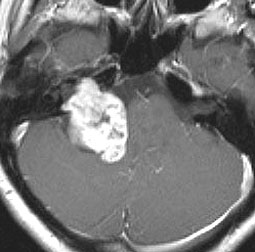

定位分割放射線治療をした聴神経腫瘍の例(左)。20%くらいの確率で放射線治療後に一時的に大きくなることがあります(中央)。やがて小さくなっていきます(右)。放射線治療後に腫瘍が大きくなっても,あわてて手術を受け入れてはいけません。

この画像はMRIのCISS/FIESTA画像というのを用いています。造影剤を使わないでも腫瘍の形と大きさが精密に解るので,経過観察には適している検査法です。

2001年に治療をした,40代女性の大きな聴神経腫瘍です。50グレイ25分割の定位放射線治療を行いました。中央が1年後,右が3年後です。徐々に縮小して手術を必要としませんでした。このサイズの聴神経腫瘍でも放射線治療は選択できるのですが,多くの場合は開頭手術をお勧めするサイズとも言えます。